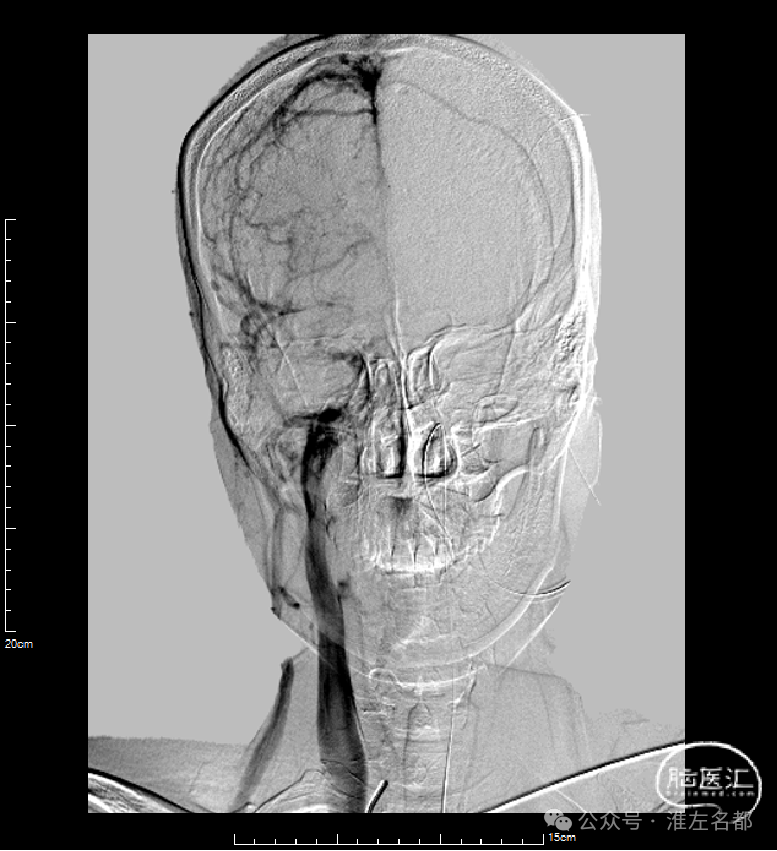

右侧股动脉穿刺置5F鞘,股动脉造影路图下穿刺右侧股静脉,置入8F鞘。6F长鞘(90cm,Cook)+6F中间管(115cm)+4F多功能管(125cm)组成同轴,泥鳅导丝导引下进入右侧颈内静脉颅底位置。泥鳅导丝超选进入右侧乙状窦和横窦,4F多功能管跟进乙状窦一段距离后难以继续前进,此时6F中间管在内衬4F管支撑下进入乙状窦,并前推进入横窦,成功建立治疗通道。

微导丝(Command 14)微导管配合,进入上矢状窦中部,交换出微导管,保留微导丝作为参照,引导后续微导丝微导管超选直窦。

微导管微导丝(Command 14)超选直窦成功后,交换出微导管。经微导丝送入3*30mm球囊,扩张直窦近段,并以BAT技术将6F中间管推送入直窦内,行血栓抽吸操作,吸出多量红色血栓。

中间管对直窦中远段抽吸后,送入微导丝,在微导丝保持通路情况下,中间管回撤抽吸直窦近段。

完成抽吸后,中间管和微导管直窦内造影均显示直窦管腔部分再通,恢复引流,但直窦近段存在狭窄。

经微导管送入并释放取栓支架(S AB 6*30mm),并在直窦取栓一次,取出少量碎小红色血栓。

微导管配合下,微导丝通过长段慢性血栓进入上矢状窦前部真腔,后交换出微导管。

3*30mm球囊扩张上矢状窦中前部管腔,辅以球囊滑动技术。

4*30mm球囊扩张上矢状窦中前部管腔,辅以球囊滑动技术。

5*30mm球囊扩张上矢状窦和右侧横窦-乙状窦,辅以球囊滑动技术。

中间管造影:上矢状窦中后部和右侧横窦-乙状窦血液引流可。